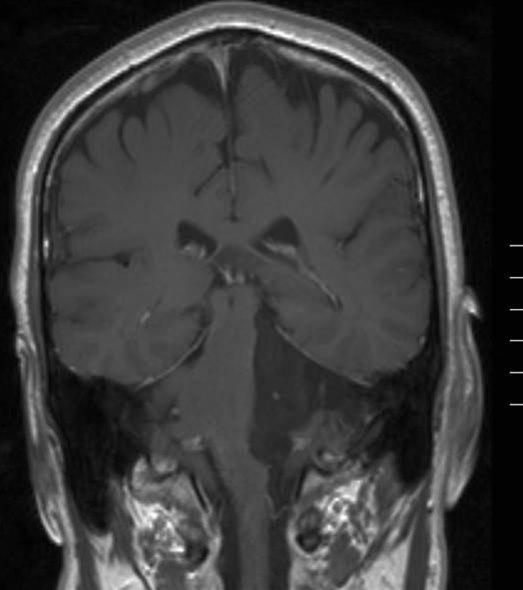

Epidermoid tumor, koronalt snitt

Gjengitt med tillatelse av Radiologisk avdeling, Universitetssykehuset Nord-Norge